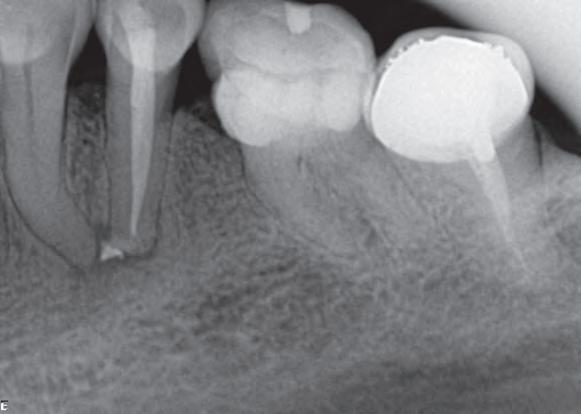

P.O. Inmediato

Prof. Dra. Patricia Ferrari

03/2018

Femenino

65 años

Periodontitis Apical Primaria Asintomática. Preparación Químico-Mecánica, Sistemas de limpieza definitiva, Terapia Fotodinámica antimicrobiana (aPDT) y Medicación Intracanal. 12/2018

Inicial